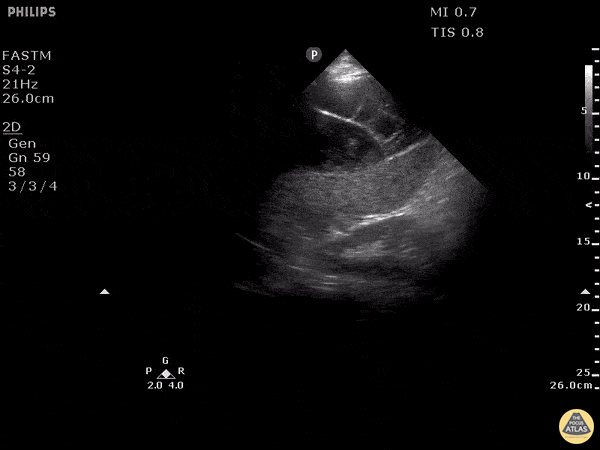

This is a clip of the LUQ performed during FAST exam following blunt trauma. It demonstrates loculated fluid around the spleen concerning for blood. CT imaging followed demonstrating a large subcapsular splenic hematoma. Image courtesy of Robert Jones DO, FACEP @RJonesSonoEM Director, Emergency Ultrasound; MetroHealth Medical Center; Professor, Case Western Reserve Medical School, Cleveland, OH View his original post here